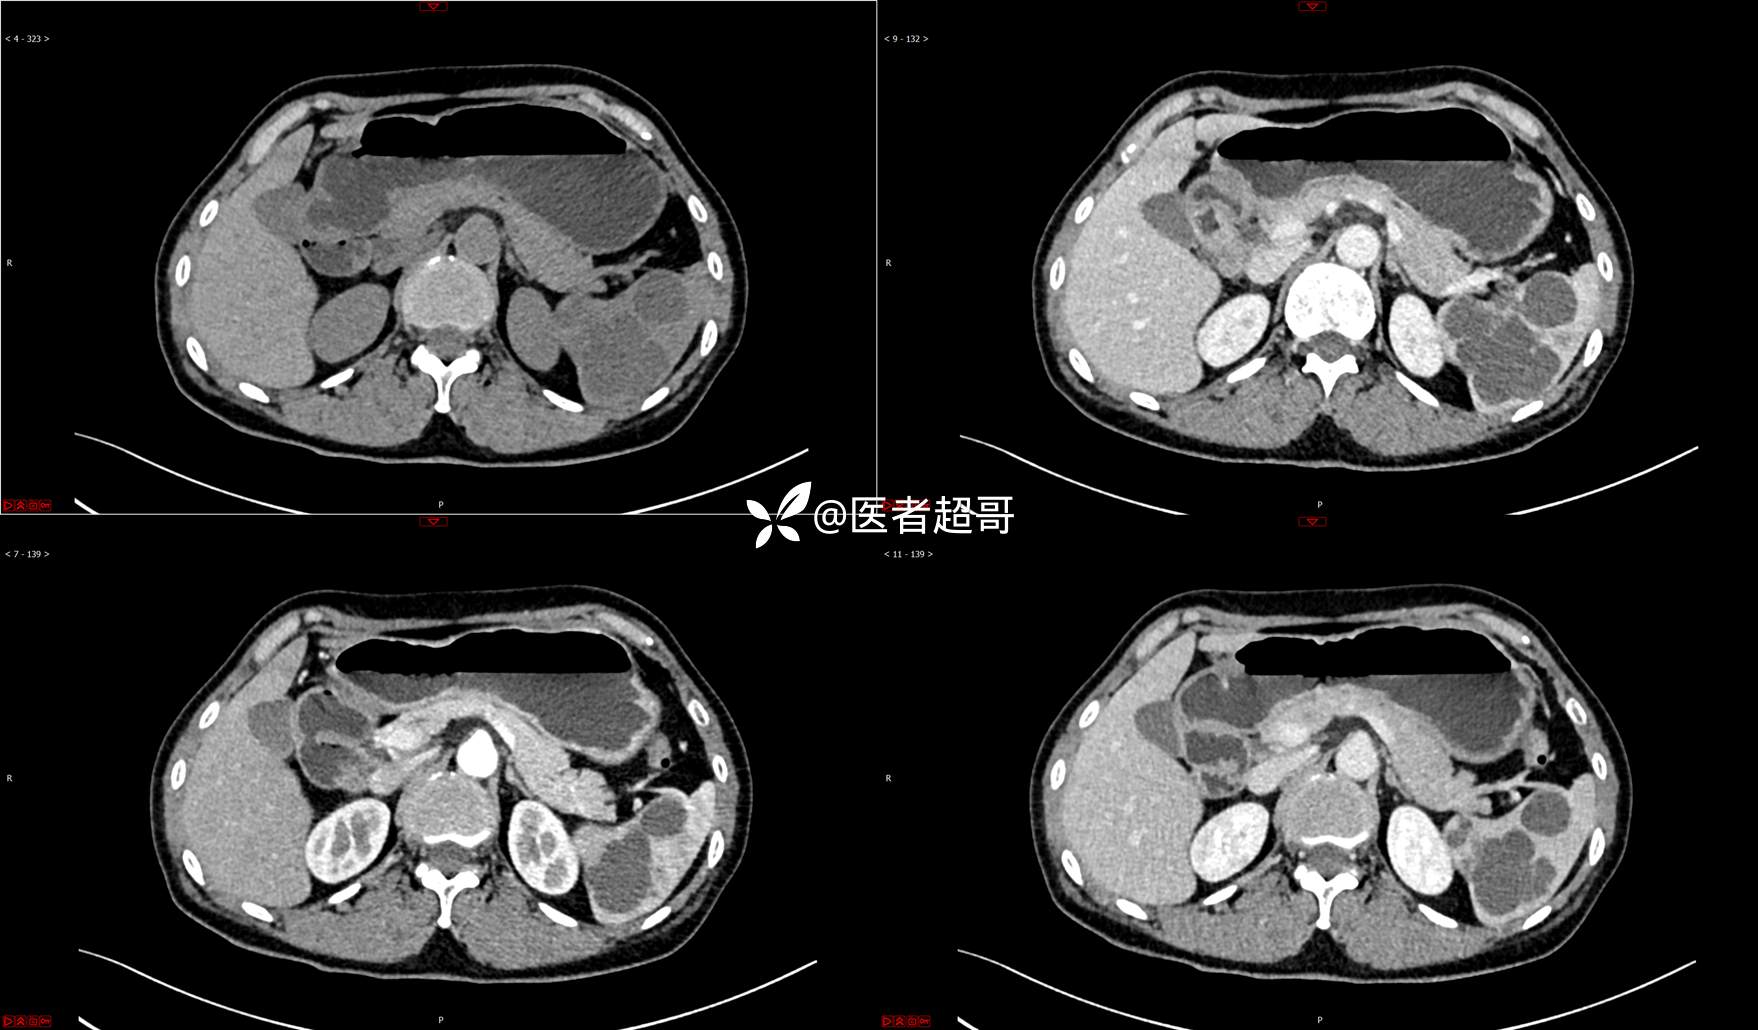

【影诊笔记739】脾脏囊性占位,查体偶发,请赏析,有病理!

女,6岁 0201215 02

主 诉:查体发现脾脏囊性占位4年。

现病史:患者4年前于人民医院查体时发现脾脏囊性占位。-04-20到我院复查,行上腹平扫+强化CT示:肝囊肿,脾脏囊实性占位,囊腺瘤?当时无明显症状,未行任何治疗。4个月前无明显原因及诱因开始偶尔出现左上腹疼痛,为隐痛,伴腰部放射痛,无腹胀、腹泻,无恶心、呕吐,无发热、畏寒、全身乏力,无胸痛、胸闷等其它不适。在外未行特殊治疗,今为求进一步诊治来我院就诊,行腹部彩超(肝、胆、胰、脾、肾)示:脾脏房囊性肿物。门诊以“脾占位性病变”收入院。发病以来,患者神志清楚,精神可,饮食可,睡眠欠佳,大小便正常,近期体重无明显变化。